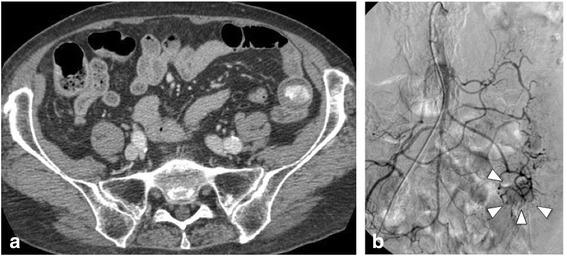

Isolated metachronous gastrointestinal metastases from advanced-stage lung cancer are rarely diagnosed on the basis of symptoms and resected. In this report, we present a case of resectable metachronous gallbladder and small intestinal metastases of lung cancer. An 86-year-old woman was treated for lung cancer with resection of the right inferior lobe. Five months after the surgery, she was re-admitted because of melena and anemia. Ultrasonography showed a gallbladder tumor with gastrointestinal hemorrhage, and laparoscopic-assisted cholecystectomy was subsequently performed. However, 2 months after this event, the patient presented again with melena and anemia and was diagnosed with a small intestinal tumor. Therefore, laparoscopic-assisted partial resection of the small intestine was performed. Immunohistochemical staining for thyroid transcription factor-1 and cytokeratin 7 confirmed that the two resected tumors were metachronous metastases of the primary lung cancer. The patient died of liver metastases 5 months after the last surgery. Our experience with this case suggests that surgical resection might not be curative but palliative for patients with isolated gallbladder and small intestinal metastases diagnosed on the basis of melena that is resistant to conservative treatment.